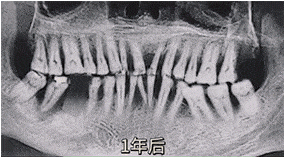

▲牙齿缺失后的变化